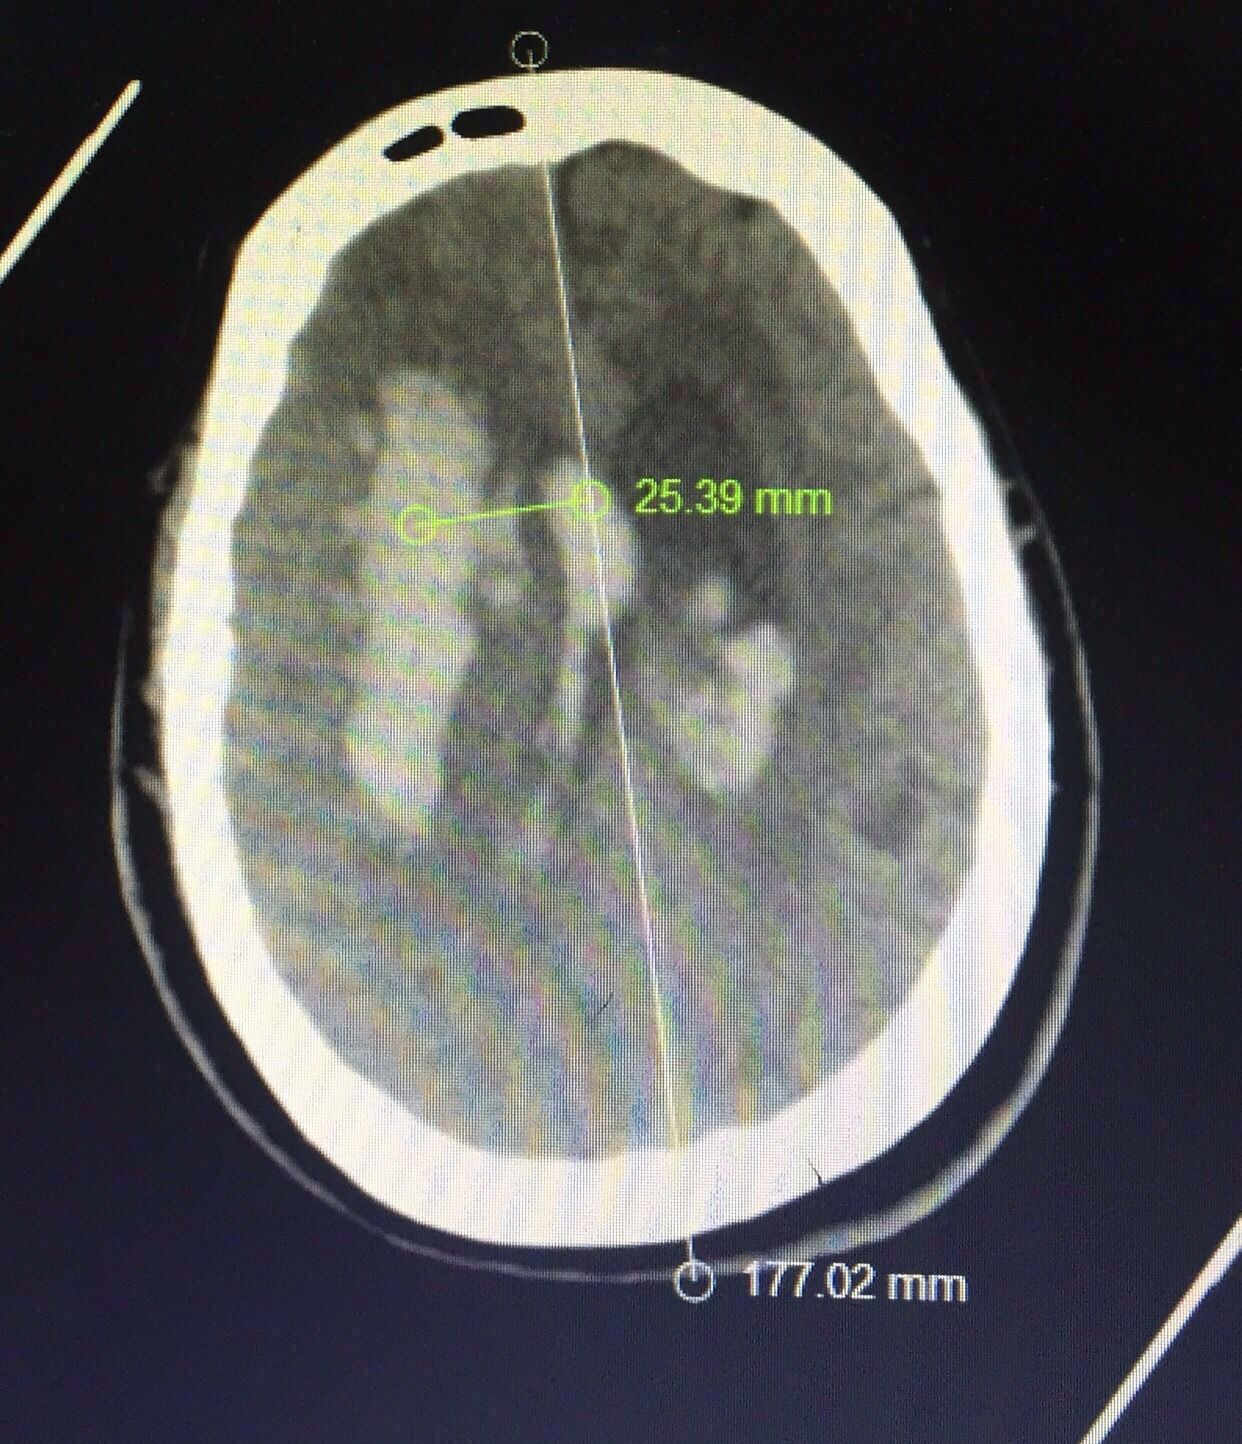

下面我们探讨一下穿刺思路↓↓

患者带呼吸机脱机困难,不易搬动,床旁行侧脑室引流的同时做血肿的穿刺,一举两得。

认真阅片可知,血肿最大层面就是脑室额角层面,EVD的靶点就是额角室间孔位置,我们把血肿靶点也定在这一层,右侧血肿内,右侧额角室间孔位置偏右,如图↑↑

经kocher点穿刺定位画线↑↑

中线旁开2.5㎝平行矢状线穿刺右侧血肿;偏内穿左侧脑室

中线旁开2.5㎝可以让穿刺管几乎游走在所有的血肿层面内↓↓↓↓↓↓4张照片